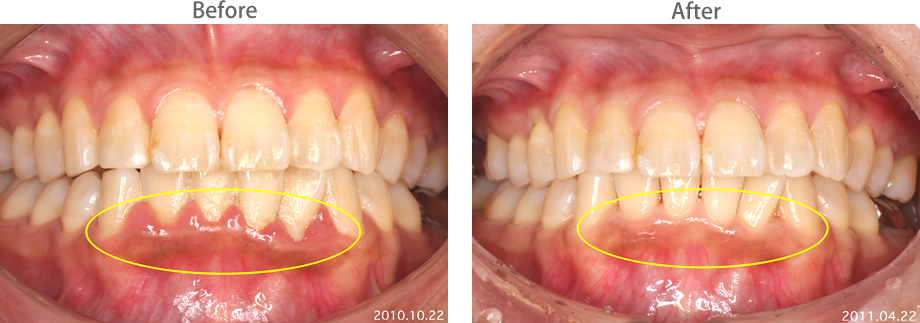

| 黄色部位に歯垢(プラーク)の付着と 歯肉炎が著しい。 |

丁寧なブラッシングと歯石除去で 歯肉炎も改善しています。 |